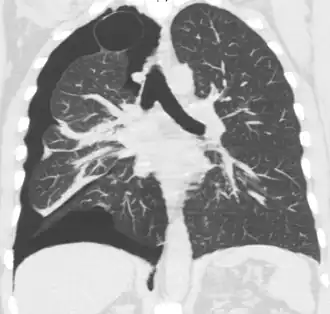

Tomografía axial computarizada

Aunque el TAC supone el gold standard en la detección de neumotórax, superando en sensibilidad y especificidad a la radiografía,[41] generalmente este no se necesita para establecer el diagnóstico de neumotórax, pero puede resultar de utilidad en situaciones particulares. En algunas patologías de las vías respiratorias, y especialmente en presencia de enfisema, es posible que ciertas estructuras pulmonares (como las cavitaciones) tengan la misma apariencia que un neumotórax en la radiografía, en cuyo caso el tratamiento específico de neumotórax no está indicado.[20] En ciertos casos de traumatismo el paciente es incapaz de permanecer en posición vertical durante la realización de la radiografía, lo cual dificulta la identificación del neumotórax en la imagen. Para estas situaciones, el TAC puede indicarse al poseer una mayor fiabilidad.[29]

Otro uso del TAC es para la identificación de lesiones concomitantes, ayudando a detectar bullas o lesiones quísticas en casos de neumotórax primario, y como herramienta de búsqueda de la causa de origen en el neumotórax secundario.[20][31]